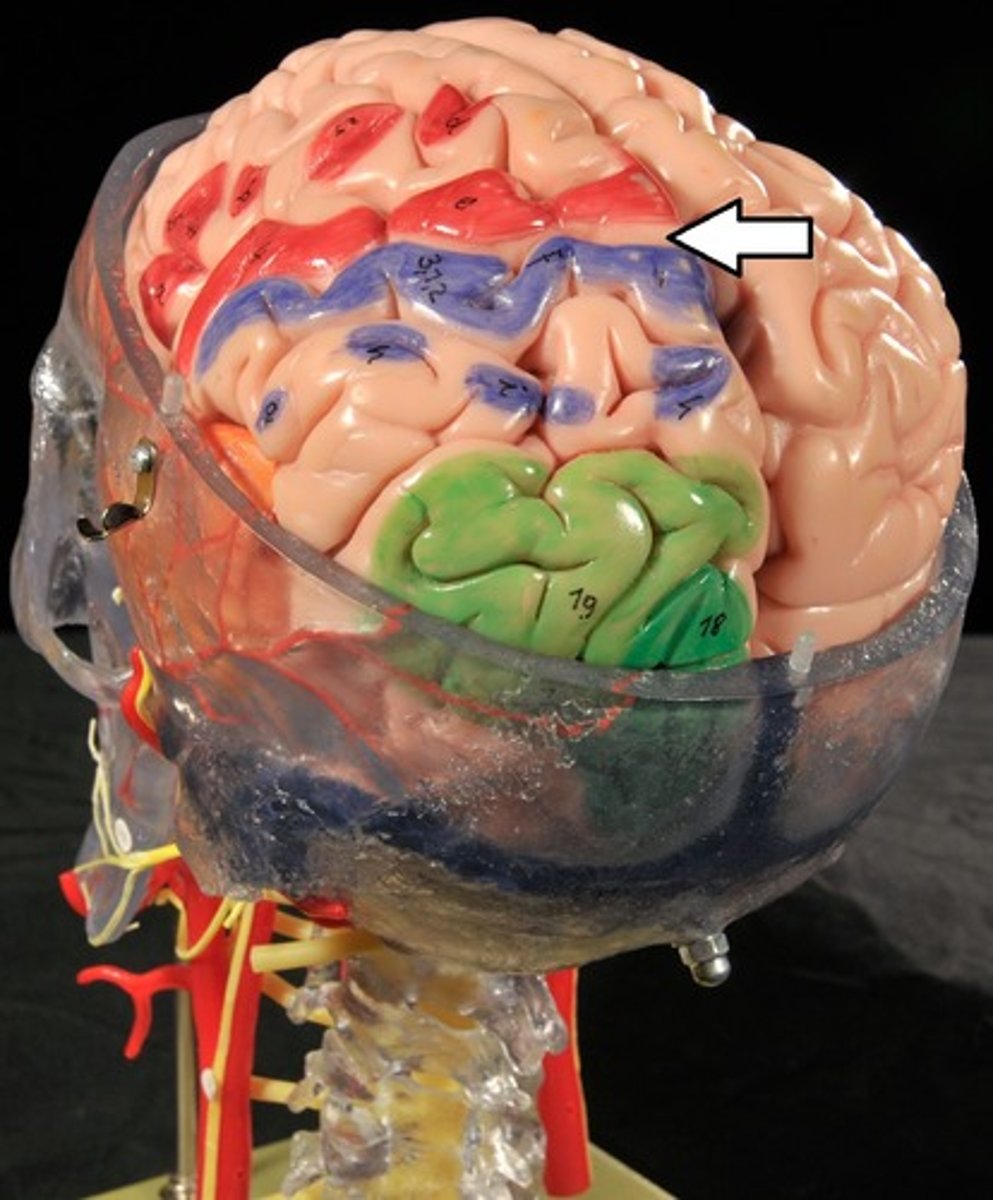

Cerebrum: Sulci and Gyri

Central Sulcus,

Precentral gyrus,

Postcentral gyrus

Central Sulcus

Precentral Gyrus

Postcentral Gyrus

Frontal lobe: motor cortex

1) Controls precise or skilled voluntary movements of our skeletal muscles

2) Also learned motor skills (repititious or patterned nature) like playing an instrument or typing

3) Is contralateral: left primary motor cortex controls muscles on right side of body & vice versa

Contralateral

Left primary motor cortex controls muscles on right side of body and vice versa

Clinical: damage to frontal lobe

Damage to localized areas of frontal lobe (such as from a stroke) paralyzes body muscles controlled by those areas.

Only voluntary control is lost, however, as muscles can still contract reflexively.